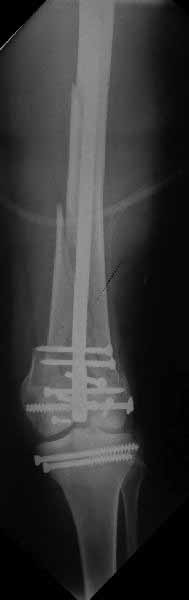

У больных как в этом случае, с вовлечением двух мыщелков правильно, что сделали вытяжение до операции. Здесь имеется флексионный компонент на другой стороне, и я бы рекомендовал операцию делать из двух доступов. Сперва фиксировать медиальную колонну custom made пластиной, обычно 1/3 тубулярной пластиной в 4.5 мм, потому что пока производители опаздывают с медиальной пластиной.

Пластину надо устанавливать на апексе перелома, иначе фрагмент начнет сползать. А на второй стороне, если имеется большой одиночный фрагмент тогда проблем не бывает, и их можно собрать компрессирующими винтами. Проблема наступает тогда когда многофрагментраность на латеральной стороне, где надо применить комбинированный метод, иногда несколькими пластинами. Или сменой позиции установки пластины, чтобы максимально прикрыть перелом и создать боковую поддержку.

Здесь пример медиальной пластины и латеральный комбинированный метод (у второго больного старый перелом тибиал плато, леченный где то и когда то)